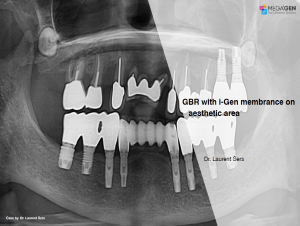

Keywords

e.g. product name, treatment solution, author, clinician name